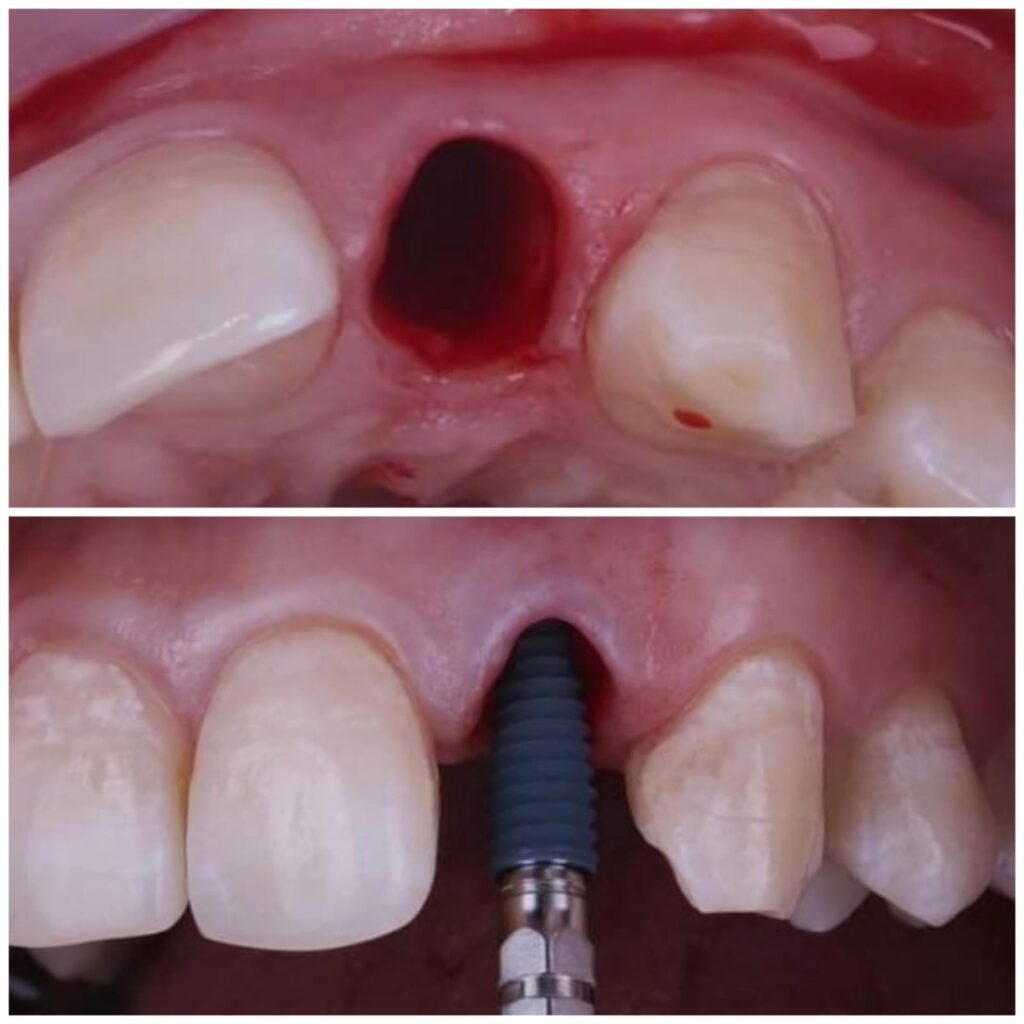

يتم تخطيط وتنفيذ إجراء زراعة الأسنان بعناية لضمان أن ترميم الأسنان يبدو طبيعيًا في الشكل واللون والمكان. نعطي الأولوية لراحة مرضانا بالإضافة إلى الجماليات. وهذا يتطلب مزيجًا مثاليًا من العبقرية الفنية والجراحية. لذلك ، يتم تنفيذ جميع حالات الزرع لدينا من قبل فريق من أطباء الأسنان التجميليين وأخصائي زراعة الأسنان.

تضيف اجهزه البانوراما الداخلية واجهزة التصوير ثلاثية الأبعاد بعدًا آخر لتقنية الزرع من خلال صورها الدقيقة للفك والأسنان. هذه الدقة ضرورية لتخطيط ووضع الغرسات. يوفر تقييمًا دقيقًا للبنى التشريحيه مثل الأعصاب وجذور الأسنان والجيوب الفكية ومعرفة طبيعة العظم وكثافة وما إلى ذلك ، مما يمنع أي احتمال للفشل الذي يحدث بسبب التشخيص الخاطئ. تم تجهيز مراكز الزرع لدينا بهذه الآلات المتطورة ، مما يمكننا من تنفيذ كل حالة من حالات الزرع بدقه عاليه وأعلى درجات النجاح.